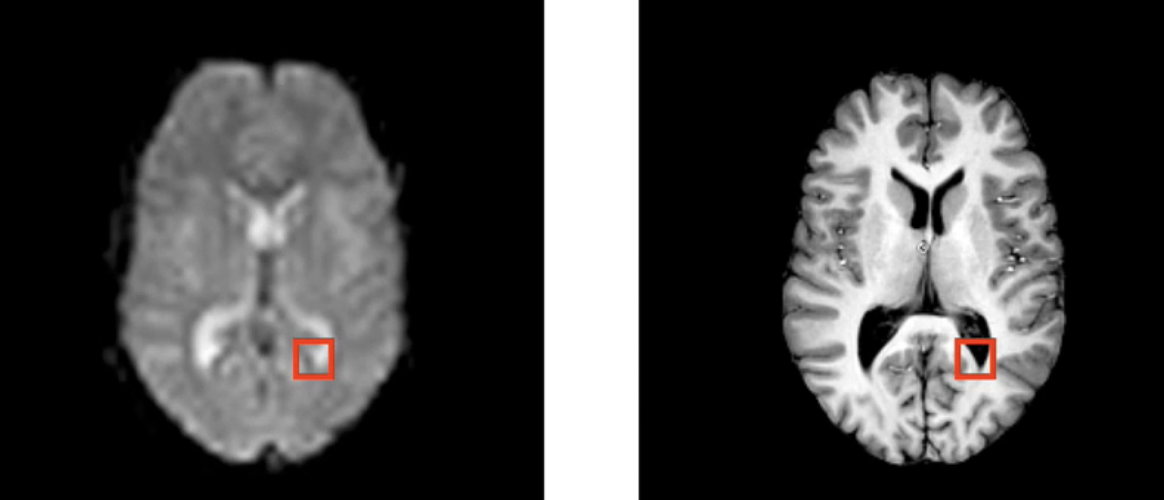

在这两张图片上,很容易看出它们没有对齐,左边相对右边倾斜,虽然我们人类视觉系统还是能把对应的解剖关系连系在一起,但是我们使用计算机分析时确不能够

因此,我们希望相同的解剖结构对齐,用坐标表示的话,希望他们在相同的坐标上。如下图

对齐这些解剖结构的过程就叫做配准(register)

我们这种从图像直接配准到参考空间,只需要一步配准,因此可以叫 single_stage registration(单阶段配准)。

对此,还有多阶段配准。

功能成像或扩散成像,然后我们也有一个特定的t1加权结构扫描主题,我们还需要将东西放入标准空间,因此我们现在有三个不同的空间,我们将进行多阶段配准,既可以在我们想要的任何空间组合之间移动,也可以让我们更好地配准

如图,我们先把epi功能像配到同一个病人的T1w上,只需要用自由度为6,线性配准进行,再把T1W配到标准空间。这时由于是不同个体,解剖差异较大,使用自由度12,非线性配准(FNIRT)